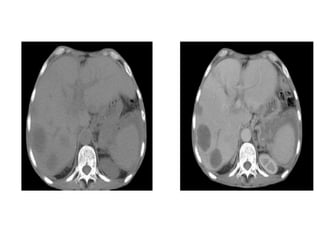

Fase sem contraste EV

Fase Arterial

Fase Portal

Fase de Equilíbrio